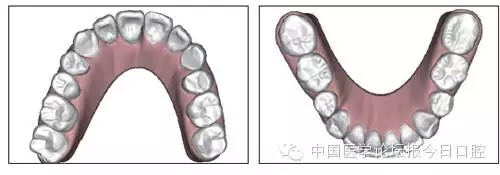

圖5 治療前ODS模型

口內(nèi)情況:恒牙列,24、34、44缺失,磨牙Ⅲ類關(guān)系,上牙列散隙,上前牙扇形漂移。前牙深覆(牙合)、深覆蓋??谇恍l(wèi)生較差,11與12間牙齦乳頭紅腫,多個(gè)牙探診有牙周袋形成,11松動(dòng)Ⅰ度,余切牙松動(dòng)(-),患者面像及口內(nèi)像如圖1、2所示。